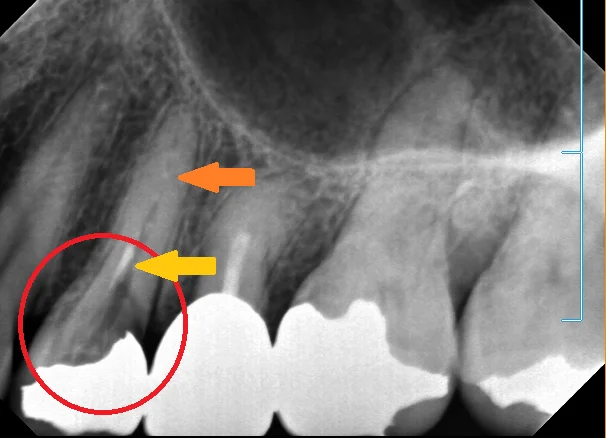

小さい奥歯(小臼歯)の白い詰め物

こんにちは。 なんだか秋口を待たずにコロナが再流行しそうですね・・・ 早いところ落ち着いてくれれば良いんですけどね。。。 さて、今日は保険適用内の治療法のコンポジットレジンの症例を載せさせていただきます。 まずは診断の根拠となったレントゲン…

続きを読む →